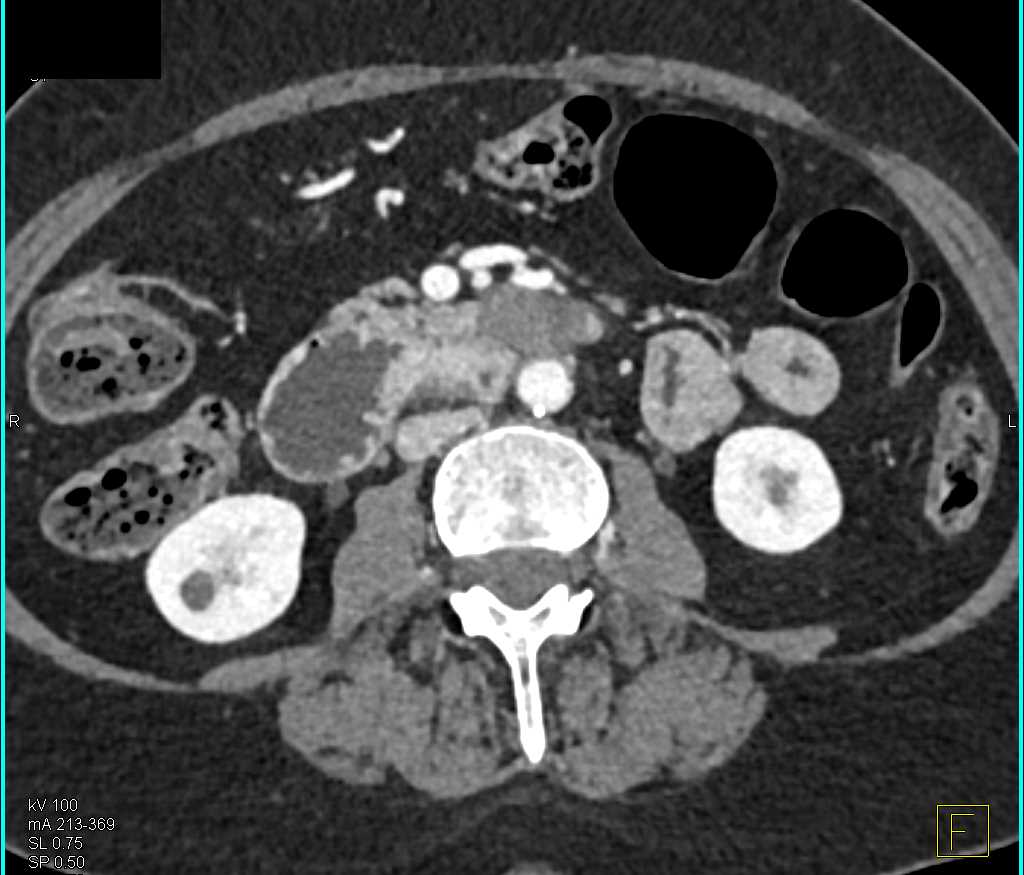

Duodenal Carcinoma with Obstruction